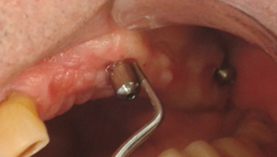

As in any pathology, the right diagnosis is essential to find a suitable treatment. The parameters to consider are: Bleeding on probing and/or Suppuration (Figure 5) and increased Probing depth (Figure 6) compared to initial exam and radiographic control. Other diagnostic methods provide little information, are more costly and complex to apply.

The presence of bleeding on probing and/or suppuration with a pressure lower than 0.25 N is a very useful parameter to diagnose mucositis and peri-implantitis. Numerous studies have found a direct link between bleeding on probing and suppuration and attachment loss around the implant. A prospective study that monitored the conditions of the peri-implant mucosa during supportive periodontal therapy found that bleeding on the same site, in over half of recall visits, in a period of two years, was related to the progression of the disease6.

Several studies have shown that an increase in probing depth entails an attachment and bone loss1,7,8,9. There is agreement that the pressure must not exceed 0.25 N, because this allows for full tissue recovery without consequences after five days10, while higher pressures can penetrate the tissues and reach the proximity of the bone crest. EUROPERIO 6o (2008) emphasized that emergence profile and contour of the reconstruction may make probing around the perimeter difficult, Therefore, it is suggested that at least one surface (mesial, distal, vestibular or lingual) should be explored11. In 2013, Serino et al.12 conducted a clinical study on 119 implants. They found that only 37% of the sites examined showed the same probing depth with and without the prosthesis in place. However, in 39% of the cases, the difference was 1 mm, and in 15% of cases it was 2 mm, which shows how difficult it is to conduct probing correctly after prosthesis placement. Additionally, in 66% of the implants, bone loss was similar in all four surfaces, while in the remaining cases it was not uniform, the vestibular surface being most affected4.